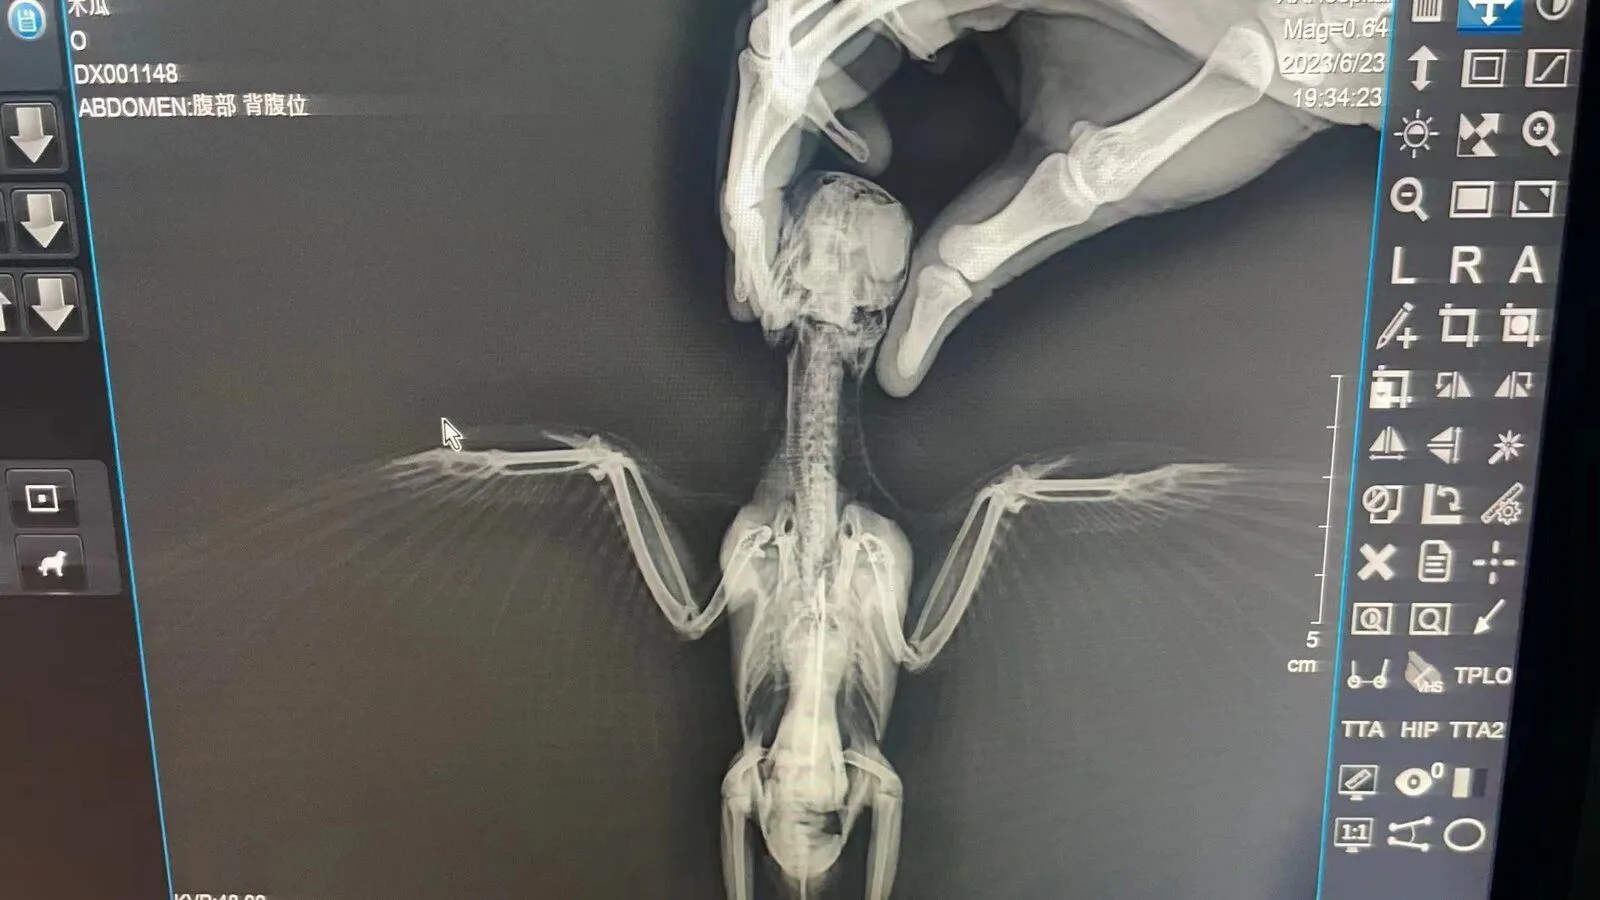

Update some pictures of the test......Pawpaw's bones are alright but stomach is bleeding. Hope he will get better!View attachment 51922View attachment 51923View attachment 51924